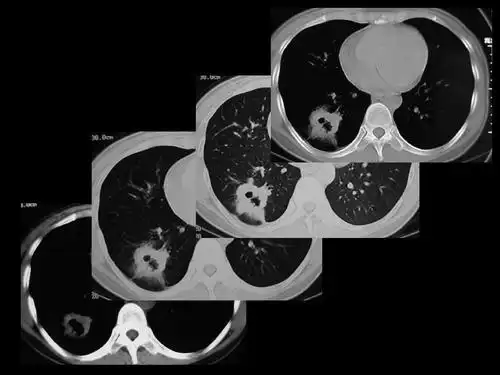

肺癌的ct诊断